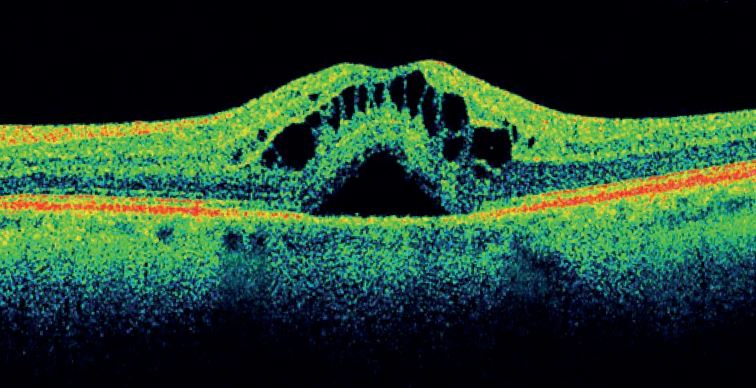

Nejmodernější neinvazivní diagnostika sítnice a zrakového nervu přístrojem 3D Maestro Topcon.